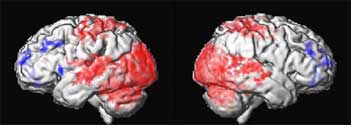

Decreased metabolism in AD compared to controls

One month of DBS compared to baseline

Positron emission tomography scans of 6 patients with Alzheimers disease

showing areas of decreased glucose utilization before surgery in

blue which are reversed with DBS after 1 month or 12 months of DBS.

Restoring glucose utilization suggests that these brain areas that were shut

down are once again active.